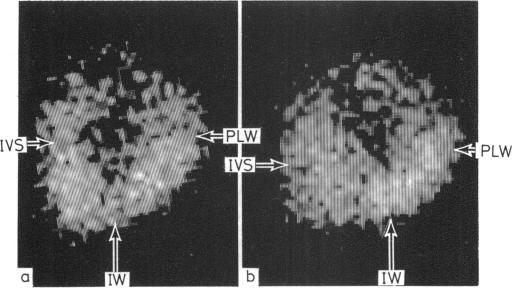

Exercise thallium-201 myocardial scintigraphy was performed in 23 patients with hypertrophic cardiomyopathy. Eighteen patients presented with chest pain which was a persistent symptom in 11. Selective coronary arteriography was performed in 16 patients and showed normal coronary arteries in 15 and insignificant luminal irregularities in one patient. Eighteen patients had abnormal scintigrams. Three had an abnormal distribution of tracer entirely attributable to asymmetric septal hypertrophy, whereas 15 had discrete tracer uptake defects which could not be explained solely by myocardial hypertrophy. In this latter group of patients three scintigraphic patterns were identified: (1) in 10 patients defects were seen in scintigrams immediately after exercise but not in delayed images obtained four to six hours later. Eight of these patients had chest pain. (2) Four patients had uptake defects seen in both initial and delayed images. One patient had chest pain. (3) In three patients, one of whom had chest pain, tracer defects were seen only in delayed images and were not apparent in the initial scintigrams. Chest pain occurred in eight out of 10 patients with scintigraphic evidence of myocardial ischaemia but was present in only three out of 13 patients with non-ischaemic scintigrams. The value of exercise thallium-201 myocardial imaging as a diagnostic technique in hypertrophic cardiomyopathy appears limited. Scintigraphic evidence of regional myocardial ischaemia in the absence of significant coronary artery disease, however, contributes to an understanding of the mechanism of angina production in patients with hypertrophic cardiomyopathy.